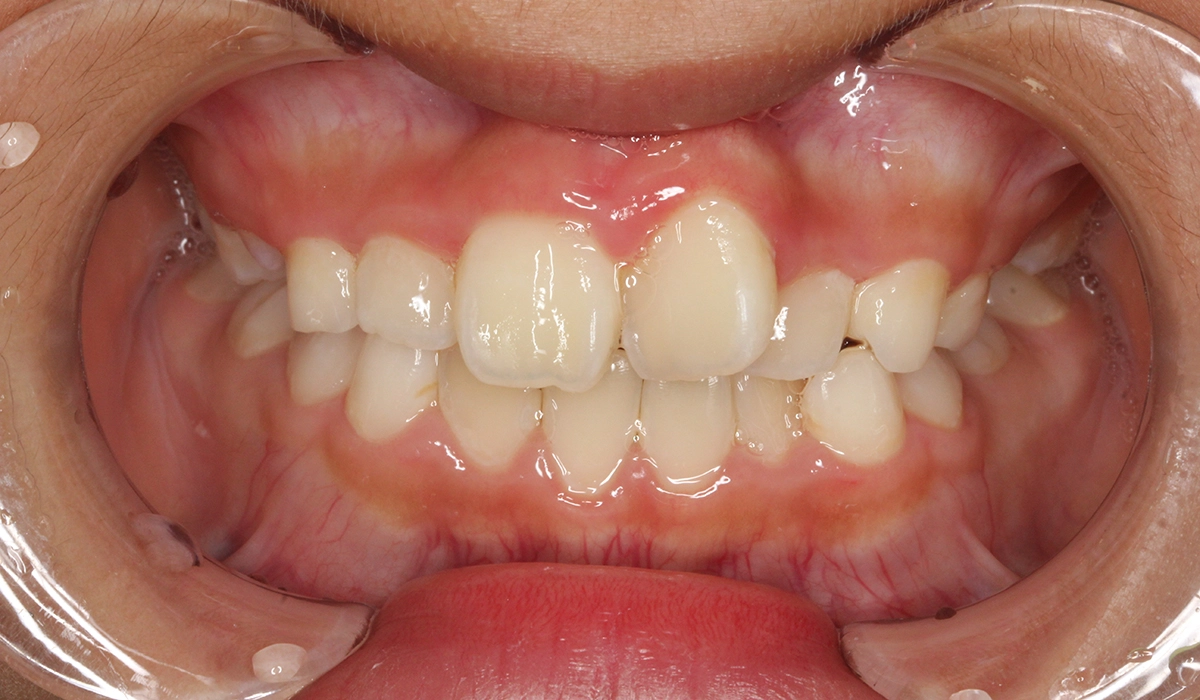

術前:正面